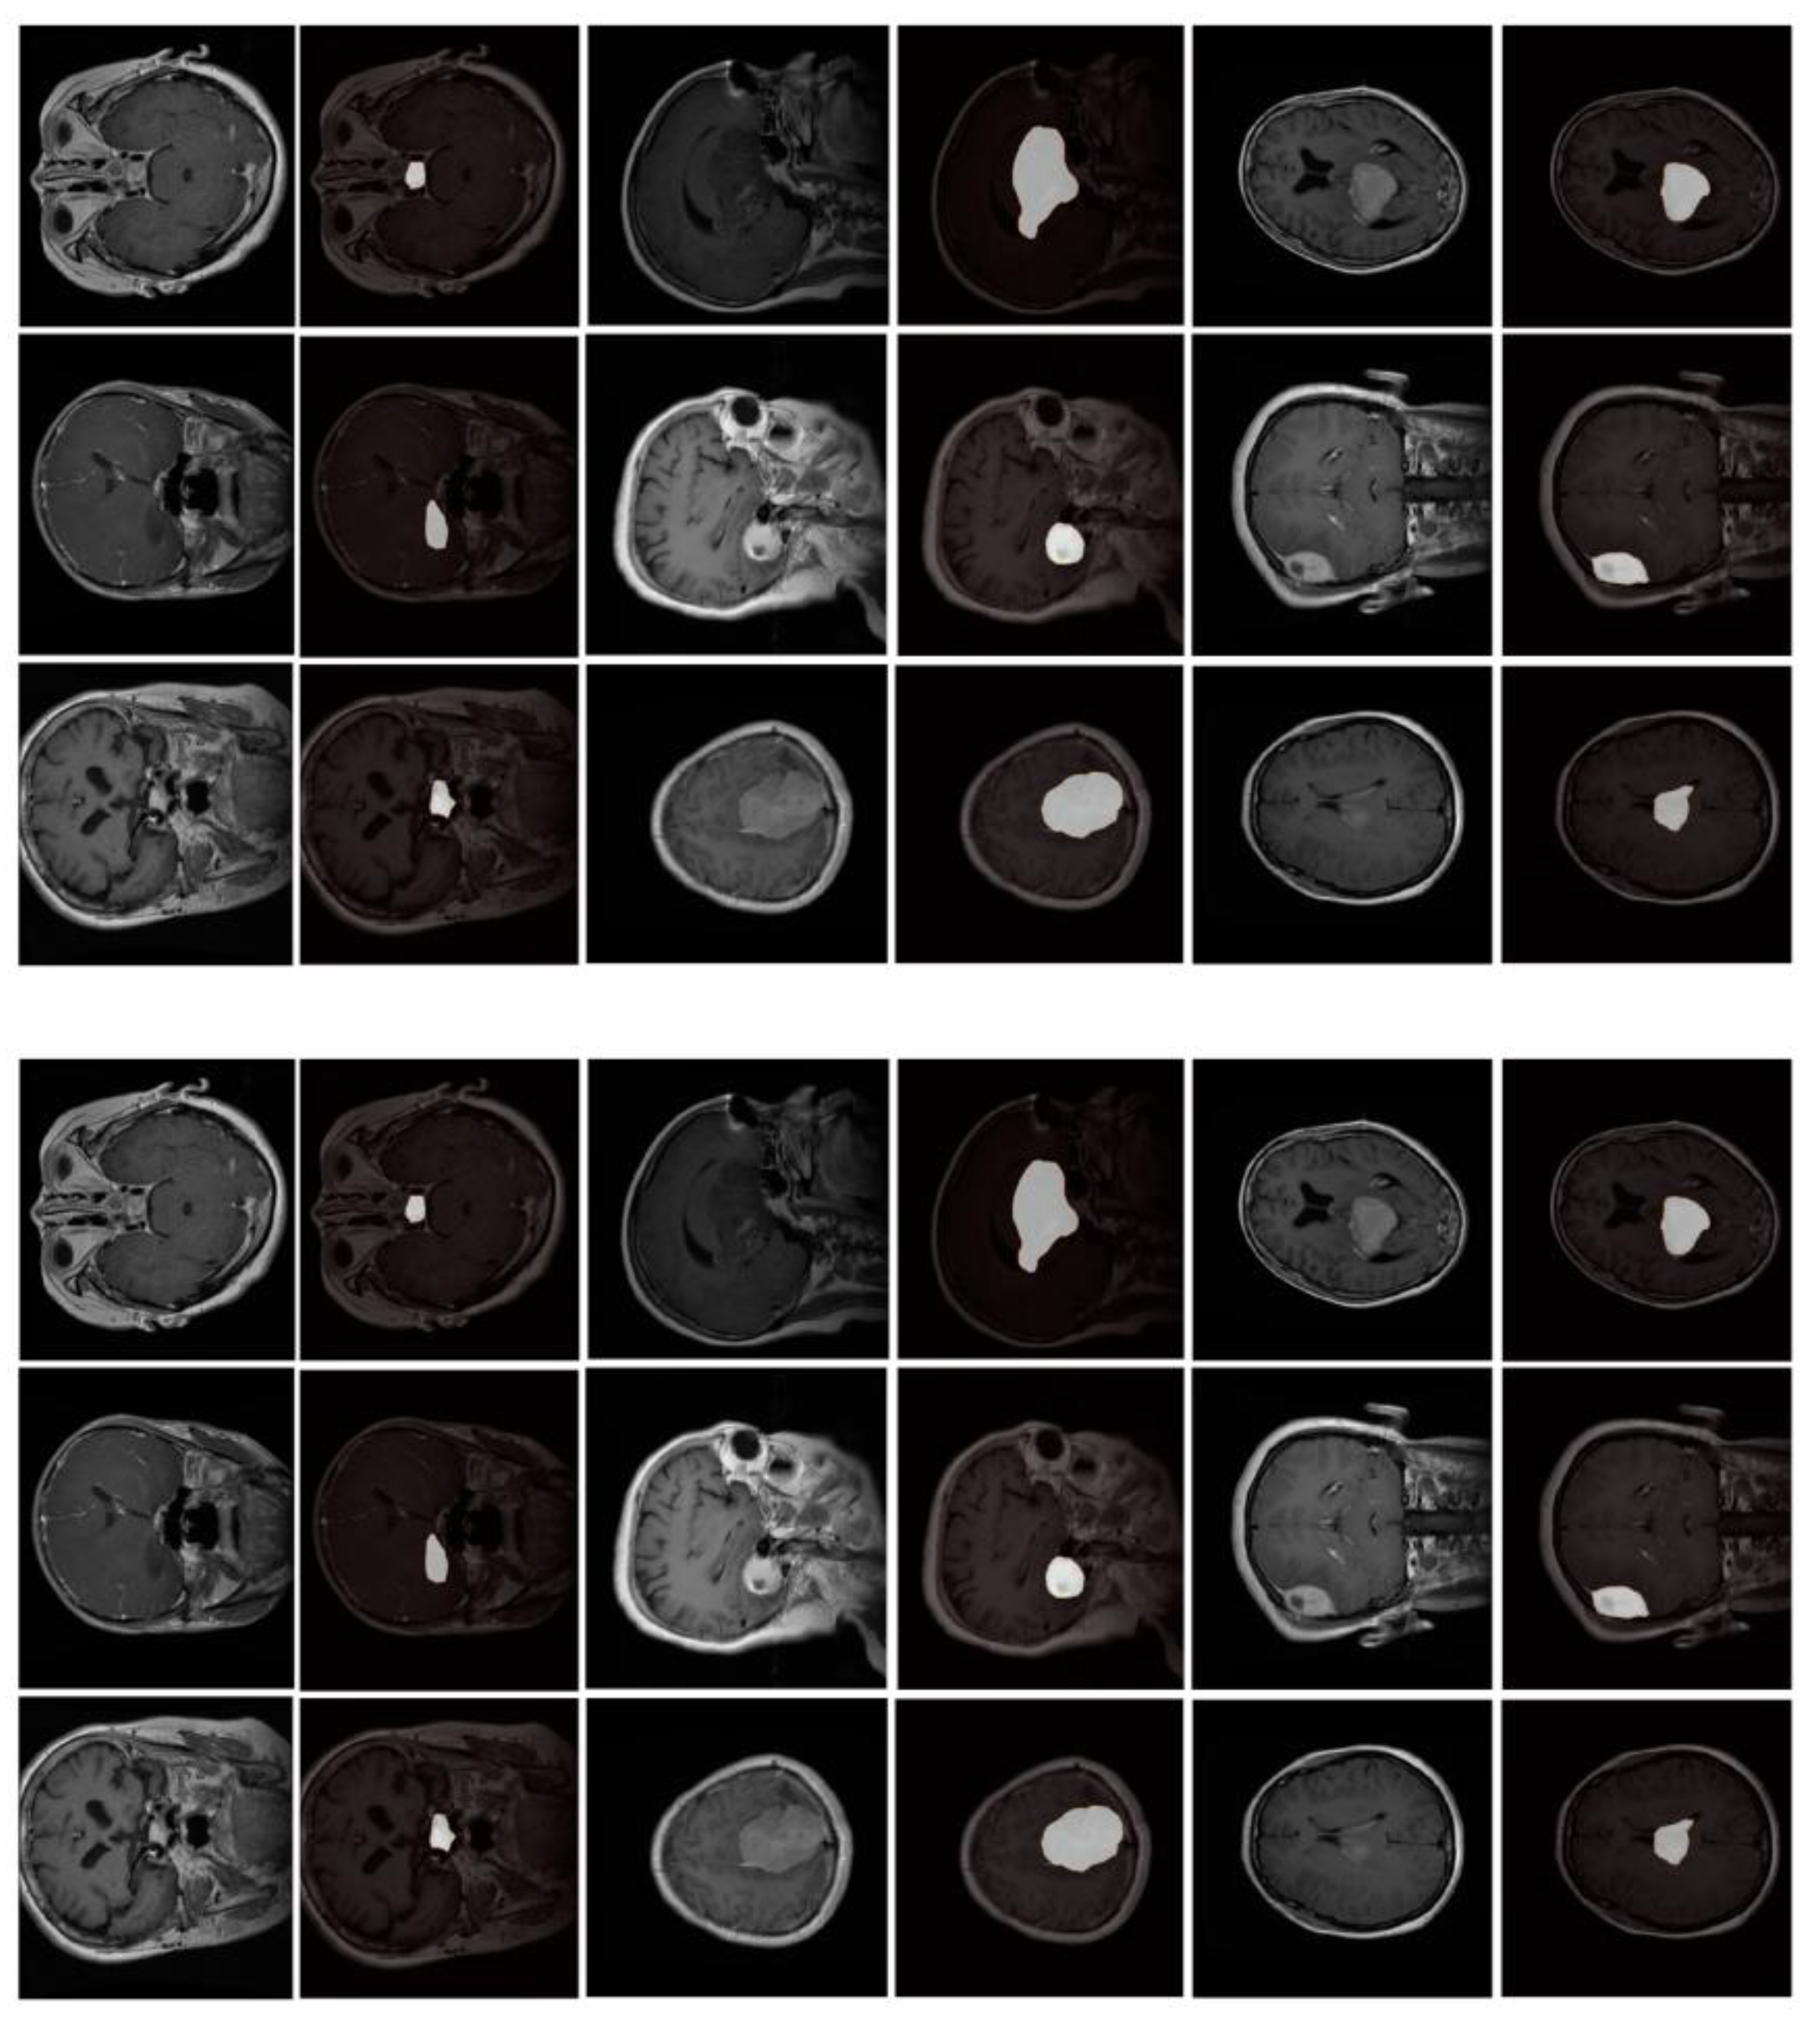

In the low-contrast subset (182 subjects), MSC-Mamba reaches a Dice score of 0.812, which is 9.1% higher than TransBTS. The model also performs better in cases with small or faint lesions. Standard 2D and 3D networks often miss thin lesion edges or small isolated regions. Earlier studies also reported that low-contrast cases cause sharp drops in accuracy for U-Net-based models. MSC-Mamba shows fewer missed regions and fewer gaps around the lesion border [14]. Figure 2 shows typical examples in which nnUNet or TransBTS fails to trace weak boundaries, while MSC-Mamba keeps the lesion connected more consistently.

Figure 2. Visual examples showing how MSC-Mamba improves boundary continuity and reduces missed regions in low-contrast scans.